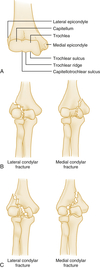

What is the more common side fractured in condylar fractures? Involvement of what section of bone makes a condylar fracture unstable?

- Lateral condyle more common - Involvement of the trochlear ridge makes it unstable - Surgical fixation if displaced >3mm Lateral, or >2mm Medial (A) Normal anatomy. (B) Lateral trochlear ridge not in fracture fragment (stable). (C) Lateral trochlear ridge included with fracture fragment (unstable).